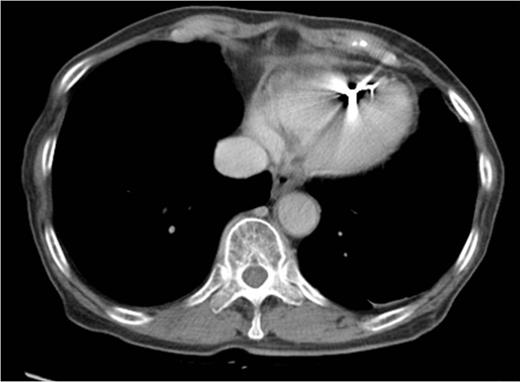

Computed tomographic coronary angiography. The right coronary artery penetrated the tumor with no significant signs of invasion (A) or displacement (B). The wire used for percutaneous pacing was placed in the right ventricle.

No specific findings for PCL have been reported. Most of the tumors seem to appear as poor enhancement structures infiltrating adjacent chambers [7]. It often involves the right atrium and the conductive system, thus leading to many types of arrhythmias [8]. On the other hand, lymphoma tends not to invade large vessels because it is softer than the other malignant tumors [9]. Indeed, in our case, the right coronary artery penetrated the tumor without any signs of invasion, even though the tumor infiltrated the adjacent right chambers. This is the first case report that has described the CTCA findings of PCL. The observation of the coronary artery without invasion by the tumor may be a significant finding of PCL. Further accumulation of cases will be needed to determine whether such findings of CTCA are useful for the diagnosis of PCL.